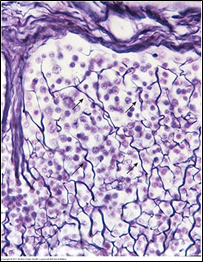

조직의 일부를 은염색(silver preparation)한 사진이다. 이 염색에 양성반응을 보이는 섬유(화살표)의 특징은?

• 은염색으로 염색되는 섬유는 그물섬유(reticular fiber)이다.

• Reticular fiber는 mesh-like network를 형성해 여러 조직과 기관의 세포 성분을 지지하는 뼈대를 구성한다.